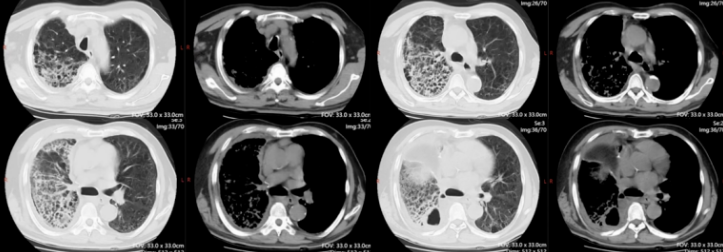

患者于2021年11月5日行射频消融治疗,11月17日胸部CT示:右下肺有渗出影(图4)。

图4 患者外院胸部CT(2021-11-17)

12月23日(入院前1天)胸部CT:右下肺渗出影进一步增大,且可见部分空洞及脓胸表现(图5)。

图5 患者外院胸部CT(2021-12-23)